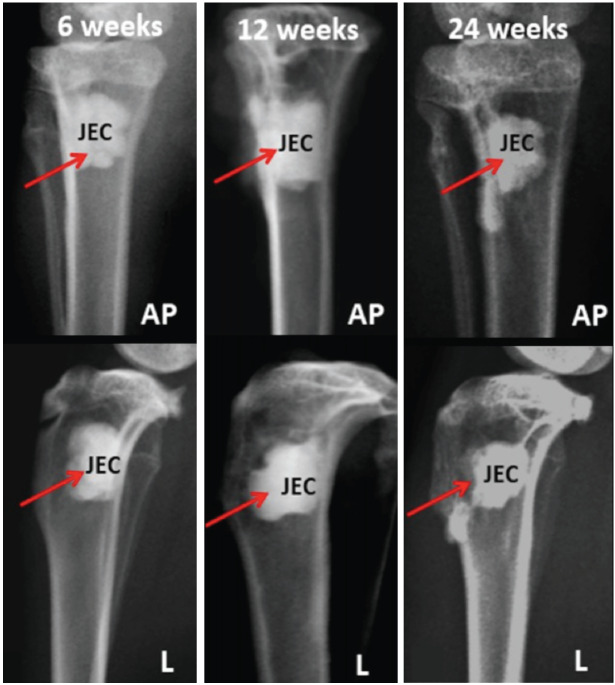

Materials and methods: A critical size defect measuring approximately 4.5mm (width) x 9.0mm (length) was surgically created at the proximal tibial metaphysis and implanted with Osteopaste, JectOS, or MIIG-X3. Following cement implantation, surrounding soft tissues were repositioned and sutured with bioabsorbable surgical suture. Bone defect healing and cement density were qualitatively and quantitatively evaluated using plain radiographs and computed tomography (CT) scans at 6, 12, and 24 weeks.

Results: The Osteopaste group showed radiographic density levels between those of JectOS and MIIG-X3. JectOS had the highest density, while Osteopaste was higher than MIIG-X3. In the Osteopaste group, new bone formation bridged the critical size defect by 12 weeks, but no bridging occurred in the other two groups at any time point. Statistical analysis showed significant differences in mean density among the groups at 6, 12, and 24 weeks (P<0.0001).